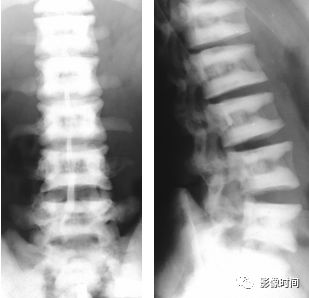

5倒置拿破仑帽征

倒置拿破仑帽征(inverted napoleon hat sign),亦有译为反拿破仑帽征

倒置拿破仑帽征是指在腰椎正位 X 线片中,腰 5 与骶 1 的投影轮廓重叠,形似倒置的拿破仑帽(蓝箭)。其中帽子的边缘是腰 5 的横突形成,而帽子的圆顶是由腰 5 的椎体投影构成。

本征象主要用于描述腰 5 椎体前滑脱(这种滑脱通常为先天性或创伤性,退变性的少见),在腰 5 未滑脱但腰骶部显著前凸时也可以出现此征象。

典型病例

22 岁男性,腰椎侧位片可见腰 5 椎体呈梯形(黑箭头),显著向前、下滑脱(黑箭),正位片形成倒置拿破仑帽征(白箭)。